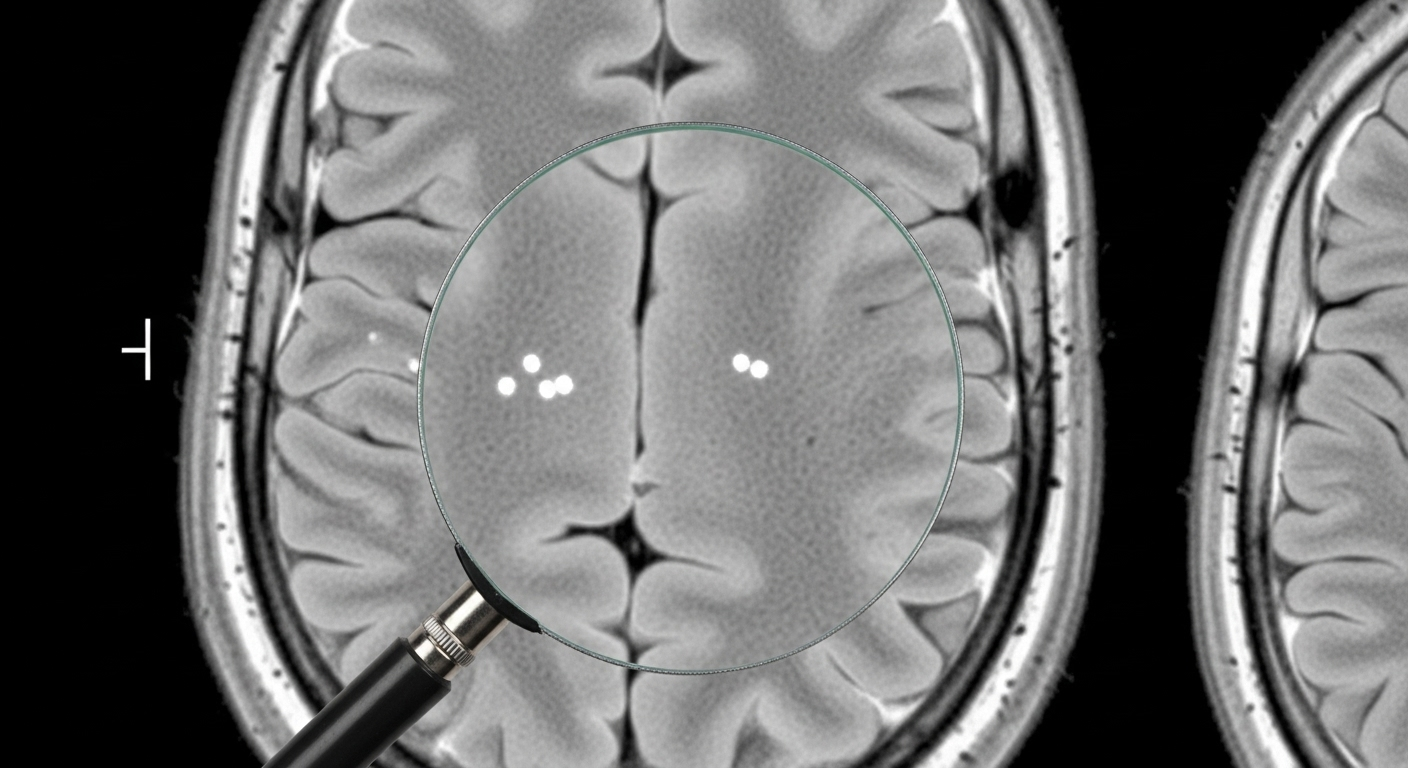

Mythe n°6 : Un AVC 'silencieux' est sans conséquence

Un AVC ‘silencieux’ est une petite lésion dans le cerveau qui ne provoque pas de symptômes évidents sur le moment. On les découvre souvent par hasard lors d’un examen d’imagerie (IRM). Mais ‘silencieux’ ne veut pas dire ‘inoffensif’. L’accumulation de ces petites attaques au fil des ans est liée à des pertes de mémoire, un déclin cognitif et un risque plus élevé de faire un AVC majeur. La prévention est donc encore plus importante pour les éviter.